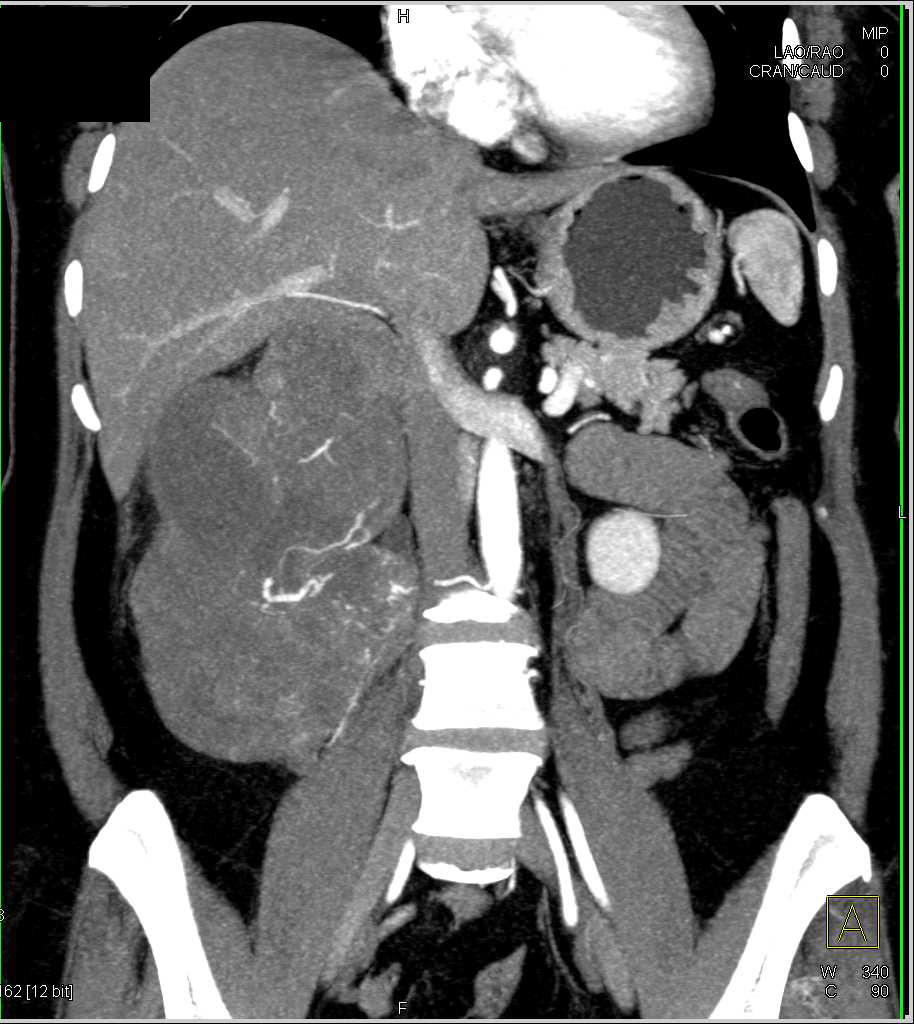

Incidental Renal Cell Carcinoma Lower Pole Right Kidney